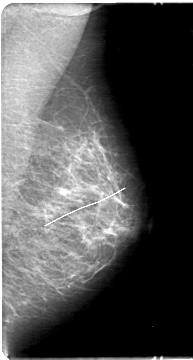

D_4029_1.RIGHT_CC

D_4029_1.LEFT_CC

LEFT_CC LINES 5386 PIXELS_PER_LINE 2731 BITS_PER_PIXEL 12 RESOLUTION 43.5 NON_OVERLAY

LEFT_MLO LINES 5386 PIXELS_PER_LINE 2881 BITS_PER_PIXEL 12 RESOLUTION 43.5 NON_OVERLAY